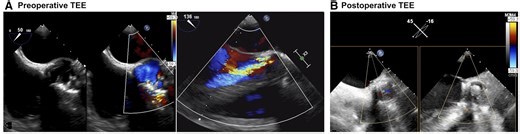

Echocardiogram - Remplacement Valve